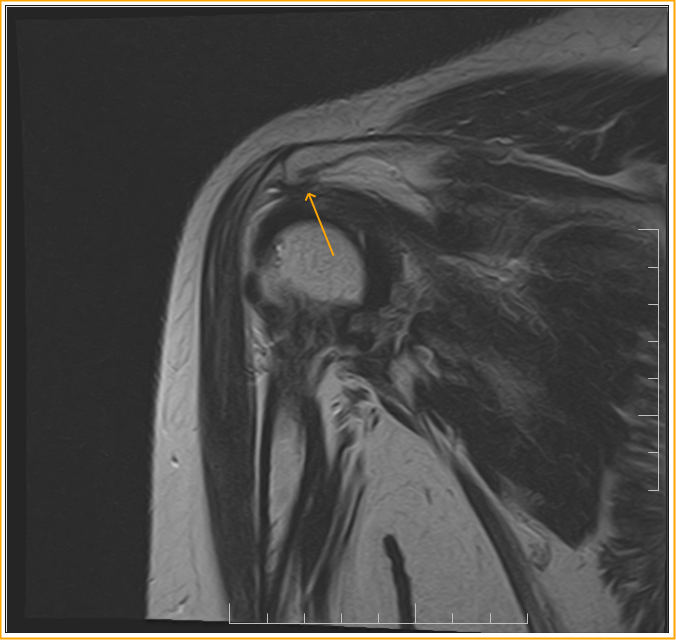

From sumerdoc.blogspot.com

Rotator Cuff Impingement Syndrome Sumer's Radiology Blog Rotator Cuff Disease Shoulder Impingement People get rotator cuff impingements for different reasons. Rotator cuff injuries are common and increase. The rotator cuff is a group of muscles and tendons that hold the shoulder joint in place and allow you to move your arm and. The rotator cuff is a common cause of pain in the shoulder. What is rotator cuff tendinopathy? Pain can happen. Rotator Cuff Disease Shoulder Impingement.